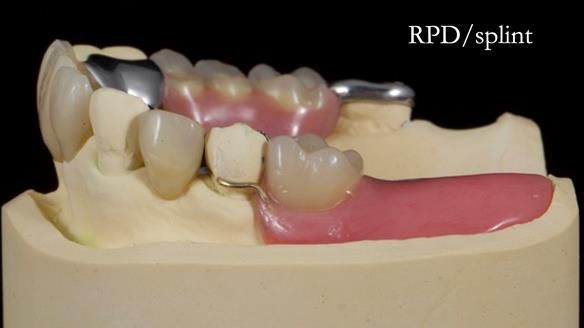

This edition features the case of Edgar, who sought help for a poorly fitting, acrylic-based partial denture that rocked, affected his speech, and caused discomfort. After considering various treatment options, including dental implants, Edgar opted for a metal-based removable partial denture, designed by myself with input from my technician, Rowan Garstang.

Treatment Process: I provided the clinical work while Rowan Garstang delivered the technical aspects. The treatment required fifteen visits to fit and review Edgar.